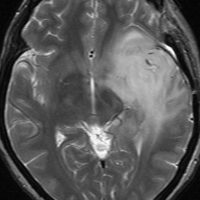

diffuse, infiltrative びまん性のもの

染み込むように左前頭側頭葉から島回に広がるAAです。T2/フレア像でにじむように広がり,ガドリニウム増強されません。グレード 2 (びまん性星細胞腫)と区別が難しいものです。

もちろん手術摘出できないもので,生検手術のみを行います。この大きさのものに60グレイの放射線治療をすれば高度の認知機能低下は避けられませんから,患者さんと照射線量をよくよく相談します。でもAAは放射線化学療法で長期生存が望めます。50-54グレイの線量が選択されます。